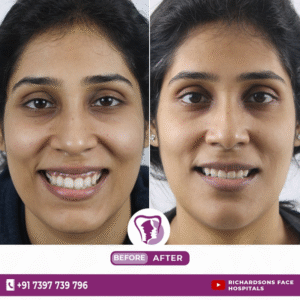

A gummy smile or excessive gingival display is a condition where an excessive amount of gingival tissue shows on the...